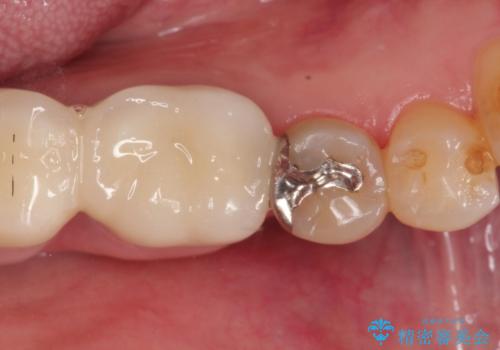

【PGAインレー】深い位置の二次カリエス

- 定期検診にて虫歯を発見したため、PGAインレーにて治療を行いました。